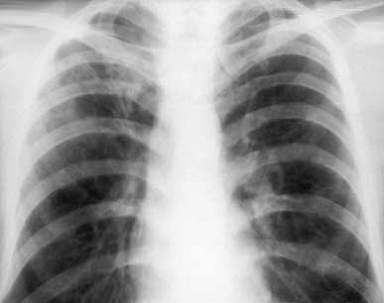

Рис. 4 Рентгенограмма ОГК и схема к ней левого легкого.

В

апикальном отделе S1–2 левого легкого определяется обогащенный легочный рисунок

за счет множественных полиморфных преимущественно среднеочаговых теней,

склонных к слиянию с нечеткими контурами; здесь же имеются плевроапикальные

наслоения. Корни легких структурны, не расширены. Купол диафрагмы четкий,

синусы свободны.

Заключение:

Очаговый туберкулез в S1–2 левого легкого в стадии инфильтрации.